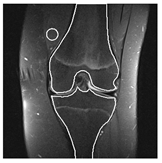

| Patient | Patient ID | Image Label | Image Prediction | Original Image | High Intensity Masking Image |

|---|---|---|---|---|---|

| Edema | 21 | Edema | Non-edema | ![]() | ![]() |

| Edema | 21 | Non-edema | Edema | ![]() | ![]() |

| Non-edema | 2 | Non-edema | Edema | ![]() | ![]() |

| Non-edema | 5 | Non-edema | Edema | ![]() | ![]() |

| Non-edema | 20 | Non-edema | Edema | ![]() | ![]() |

| Non-edema | 30 | Non-edema | Edema | ![]() | ![]() |